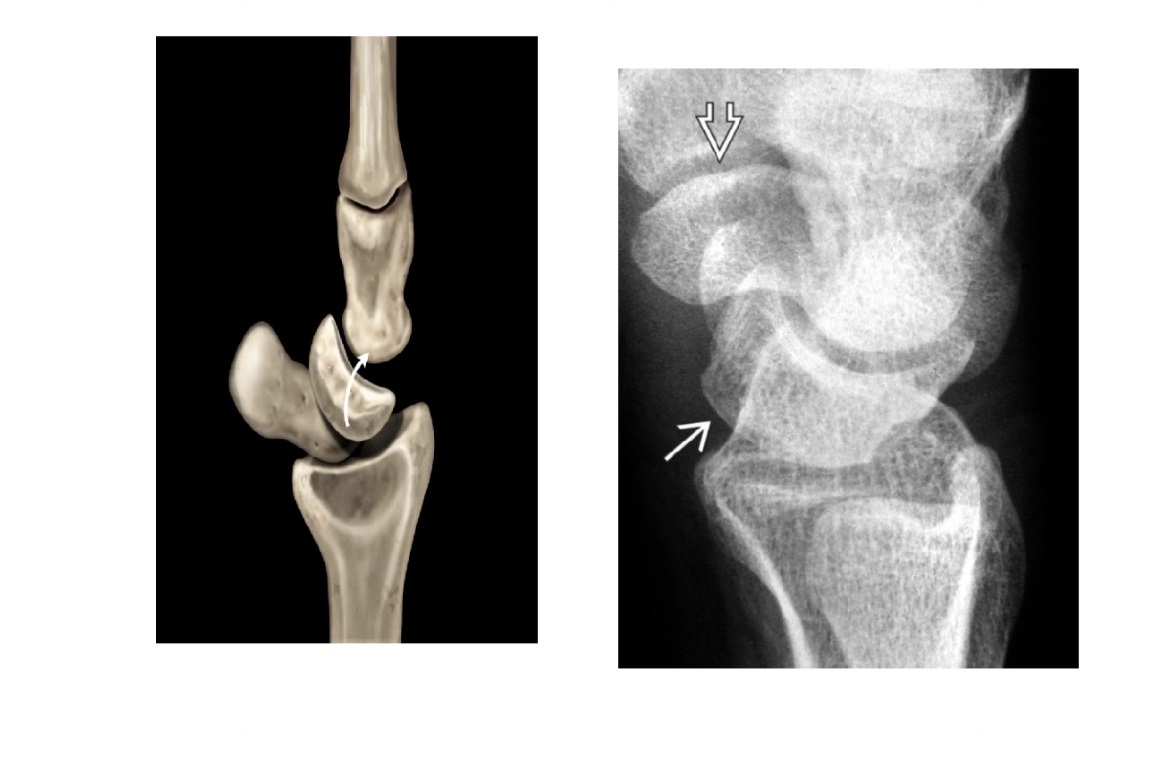

5

Q